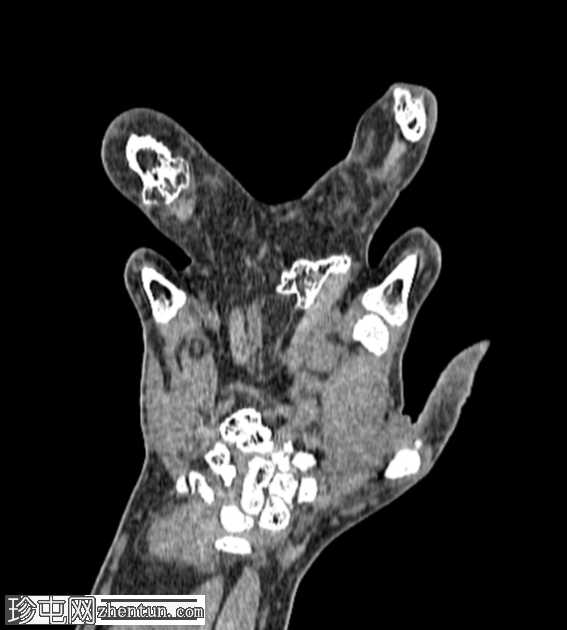

无名指和中指明显增大。患者掌骨和指骨骨质增生肥大,并伴有周围皮下脂肪过度增生。

骨窗

CT 扫描显示骨质过度生长和肥大、皮下脂肪过度生长以及神经纤维脂肪瘤性错构瘤。